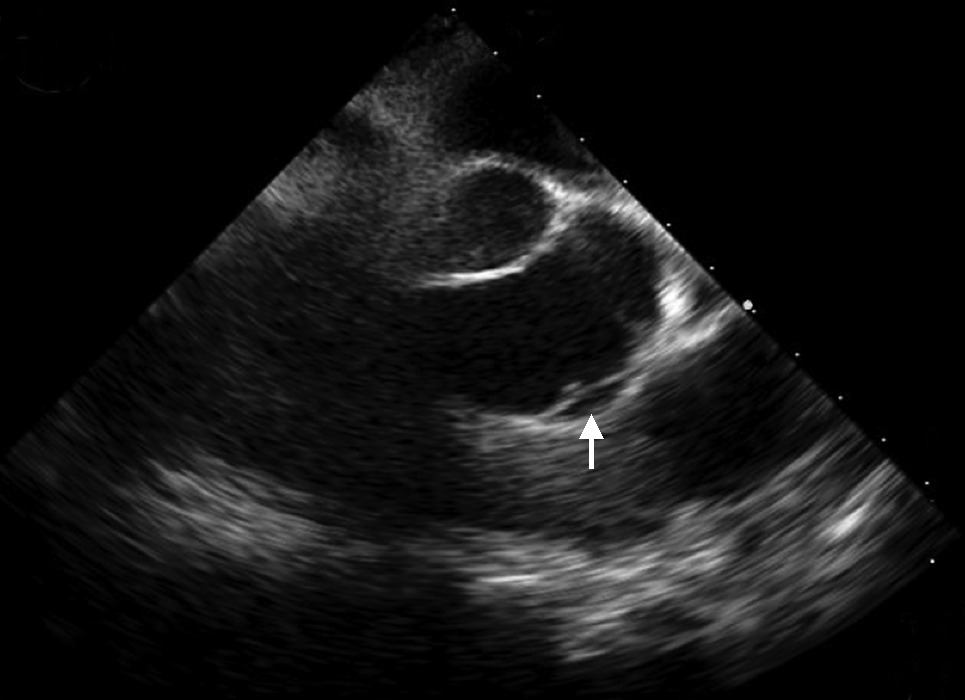

患者,男性,67岁,主因“头晕、胸痛伴一过性意识障碍3 d”入院。患者2019年4月19日13:00步行时突发头晕,伴胸背部疼痛,大汗、呼吸困难,2~3 s后一过性意识丧失,约20 min后恢复意识。14:00患者再发心前区压榨样疼痛,向胸背部放射,至当地医院急诊测血压61/37 mmHg(1 mmHg=0.133 kPa),心率114次/min,肝肾功能:谷丙转氨酶(ALT)156 U/L,谷草转氨酶(AST)262 U/L,肌酐 111 μmol/L;心肌酶(-),心电图未见明显异常(图1)。胸部CT:心包积液,主动脉根部增粗。UCG:左室肥厚,左室节段性室壁运动异常,中量心包积液,LVEF 38%,予多巴胺及去甲肾上腺素静脉泵入,维持血压 90~110/70~80 mmHg。4月20日中午转至北京某三甲医院,查肝肾功:ALT 2 139 U/L,AST 1 534 U/L,肌酐230 μmol/L,肌钙蛋白I:1.2 ng/ml,D-二聚体 2094 ng/ml(参考范围0~243 ng/ml)。床旁UCG:LVEF 60%,中量心包积液,主动脉瓣轻度返流。主动脉CTA:未见明显夹层。2019年4月20日晚转入本院抢救室,入院血压 71/52 mmHg,心率92次/min,SpO2 98%,查肌酐206 μmol/L,心电图可疑V1~V2 ST段可疑弓背向上抬高,T波低平(图2),肌钙蛋白I 1.659 μg/L。行诊断性心包穿刺得血性心包积液。04月21日床旁UCG:少量心包积液;下腔静脉增宽;左室肥厚;心包腔内可疑占位,血栓可能性大(图3A、B)。腹主动脉超声:腹主动脉粥样硬化伴多发斑块形成。给予补液、血管活性药维持血压,加用天晴甘美及多烯磷脂酰胆碱保肝,监测肝酶及肌酐缓慢下降,为进一步诊治收入我科。既往高血压病10年,收缩压最高170 mmHg,口服硝苯地平缓释片1片/d,收缩压控制在140~150 mmHg左右;有大量吸烟史,家族史无殊。入院体格检查:血压129/88 mmHg,心率71次/min,双下肺无罗音,心音略低钝,各瓣膜区无杂音。肝区叩击痛。双下肢不肿。

另外本患病初为中量心包积液,此后复查心脏超声积液逐渐减少,而左室射血分数却逐渐恢复,结合本院床旁心脏超声可见心包腔内随心脏收缩舒张飘动的条索样中低回声占位,考虑为心包内血液形成血栓,导致心包腔内液体成分减少,同时血栓在一定程度上可能堵塞了破口,从而减少了主动脉内血液向心包腔内的持续流入,减轻了心包填塞程度,患者的左室射血分数、血压也逐渐恢复。